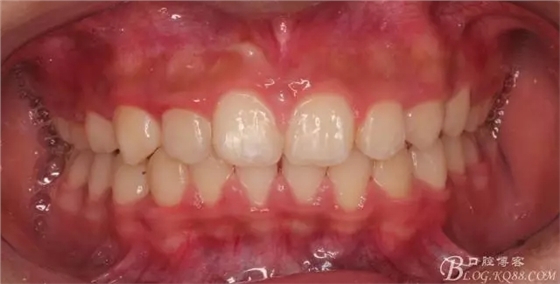

看看口內(nèi)照吧!真象“大暴牙”v假象“大暴牙”

640.webp.jpg

三度深覆合,三度深覆蓋,尖牙,磨牙均二類關(guān)系!